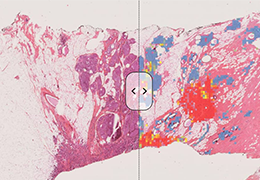

成像智能。

Eclipse 成像智能功能提供强大的处理能力和最佳质量的影像,同时减少质量错误并提高剂量效率。

凭借 AI、专有算法和先进的影像处理能力,提供出色的影像质量和无与伦比的诊断信心。

提供相配视图选项,以减少所需的曝光次数,并提供更清晰的感兴趣区域视图。